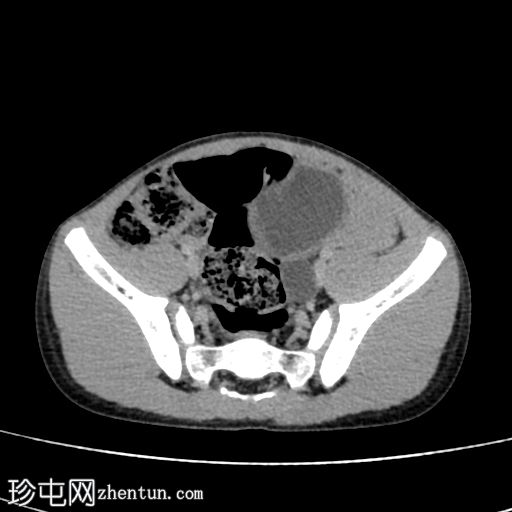

轴位增强CT(门静脉期)

2.jpg

在这张多期增强CT图像中,我们可以观察到肾盏、肾盂以及左侧输尿管全程扩张。

未见感染或其他相关征象。

本例为原发性巨输尿管。整个泌尿系统的扩张是诊断的关键。